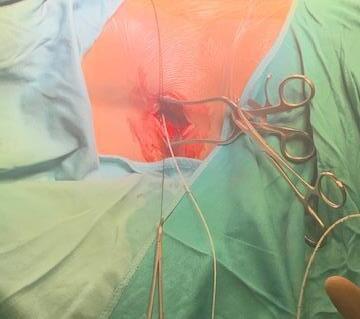

SDR involves surgically accessing the spinal cord (typically in the lumbosacral region, L2 to S1 or S2).The dorsal (sensory) nerve roots are carefully identified and then divided into smaller bundles called rootlets.

Adductor Longus L2, L3

Vastus Lateralis L3,L4

Tibialis Anterior L4, L5

Peroneus longus L5, S1

Gastrocnemius S1, S2

Abductor hallucis S1, S2

Sphincter S2